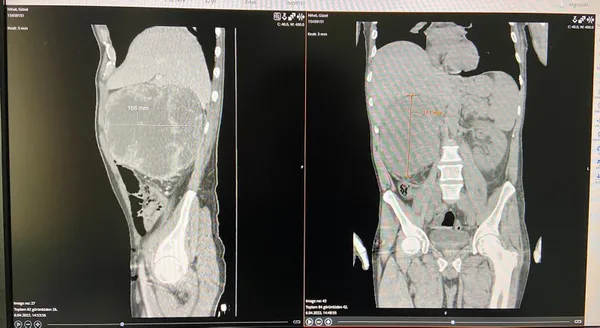

Yakutiye ilçesi Hilalkent semtinde oturan Nihat Güzel, baş dönmesi, halsizlik ve kusma gibi şikayetlerle Erzurum Şehir Hastanesi'ne gitti. Ürolog operatör Dr. Fatih Akkaş'ın yaptığı muayenede sağ yumurtalığında şişlik belirlenen Güzel'in çekilen ultrason ve filmlerinde karnında 20 santimlik kitle olduğu tespit edildi.

Nihat Güzel'in ilk muayenesinde sağ yumurtalığında şişlik belirlediklerini anlatan Dr. Akkaş, "Sağ taraftaki şişlik bizim aklımıza karın içerisinde baskı yapan kitle olabileceğini getirdi. Yapılan tetkiklerde ve çekilen filmlerde sağ tarafta 20 santimetre boyutunda bir kitle tespit edildi.

Böbrek, karaciğer, büyük damarlar ile atardamara yapışık olan kitlenin vücuda yayılmadığını belirledik ve operasyonla çıkarılabileceğini gördük. Gerekli hazırlıklardan sonra yapılan ameliyatla kitleyi çıkardık. 20 santim büyüklüğündeki kitle, biraz daha geç kalınsaydı vücuda yayılma ihtimali vardı.